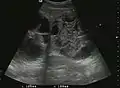

Hepatocellular carcinoma (HCC)

It is the most common liver malignancy. It develops secondary to cirrhosis therefore, ultrasound examination every 6 months combined with alpha fetoprotein (AFP) determination is an effective method for early detection and treatment monitoring for this type of tumor . Clinically, HCC overlaps with advanced liver cirrhosis (long evolution, repeated vascular and parenchymal decompensation, sometimes bleeding due to variceal leakage) in addition to accelerated weight loss in the recent past and lack of appetite.

HCC appearance on 2D ultrasound is that of a solid tumor, with imprecise delineation, with heterogeneous structure, uni- or multilocular (encephaloid form). An "infiltrative" type is also described which is difficult to discriminate from liver nodular reconstruction in cirrhosis. Typically HCC invades liver vessels, primarily the portal veins but also the hepatic veins . Doppler examination detects a high speed arterial flow and low impedance index (correlated with described changes in tumor angiogenesis). The spatial distribution of the vessels is irregular, disordered. CEUS examination shows hyperenhancement of the lesion during the arterial phase. During the portal venous phase there is a specific "wash out" of ultrasound contrast agent (UCA) and the tumor appears hypoechoic during the late phase. Poorly differentiated tumors may have a stronger wash out leading to an isoechoic appearance to the liver parenchyma during portal venous phase. This appearance was found in approx. 30% of cases. The described changes have diagnostic value in liver nodules larger than 2 cm.